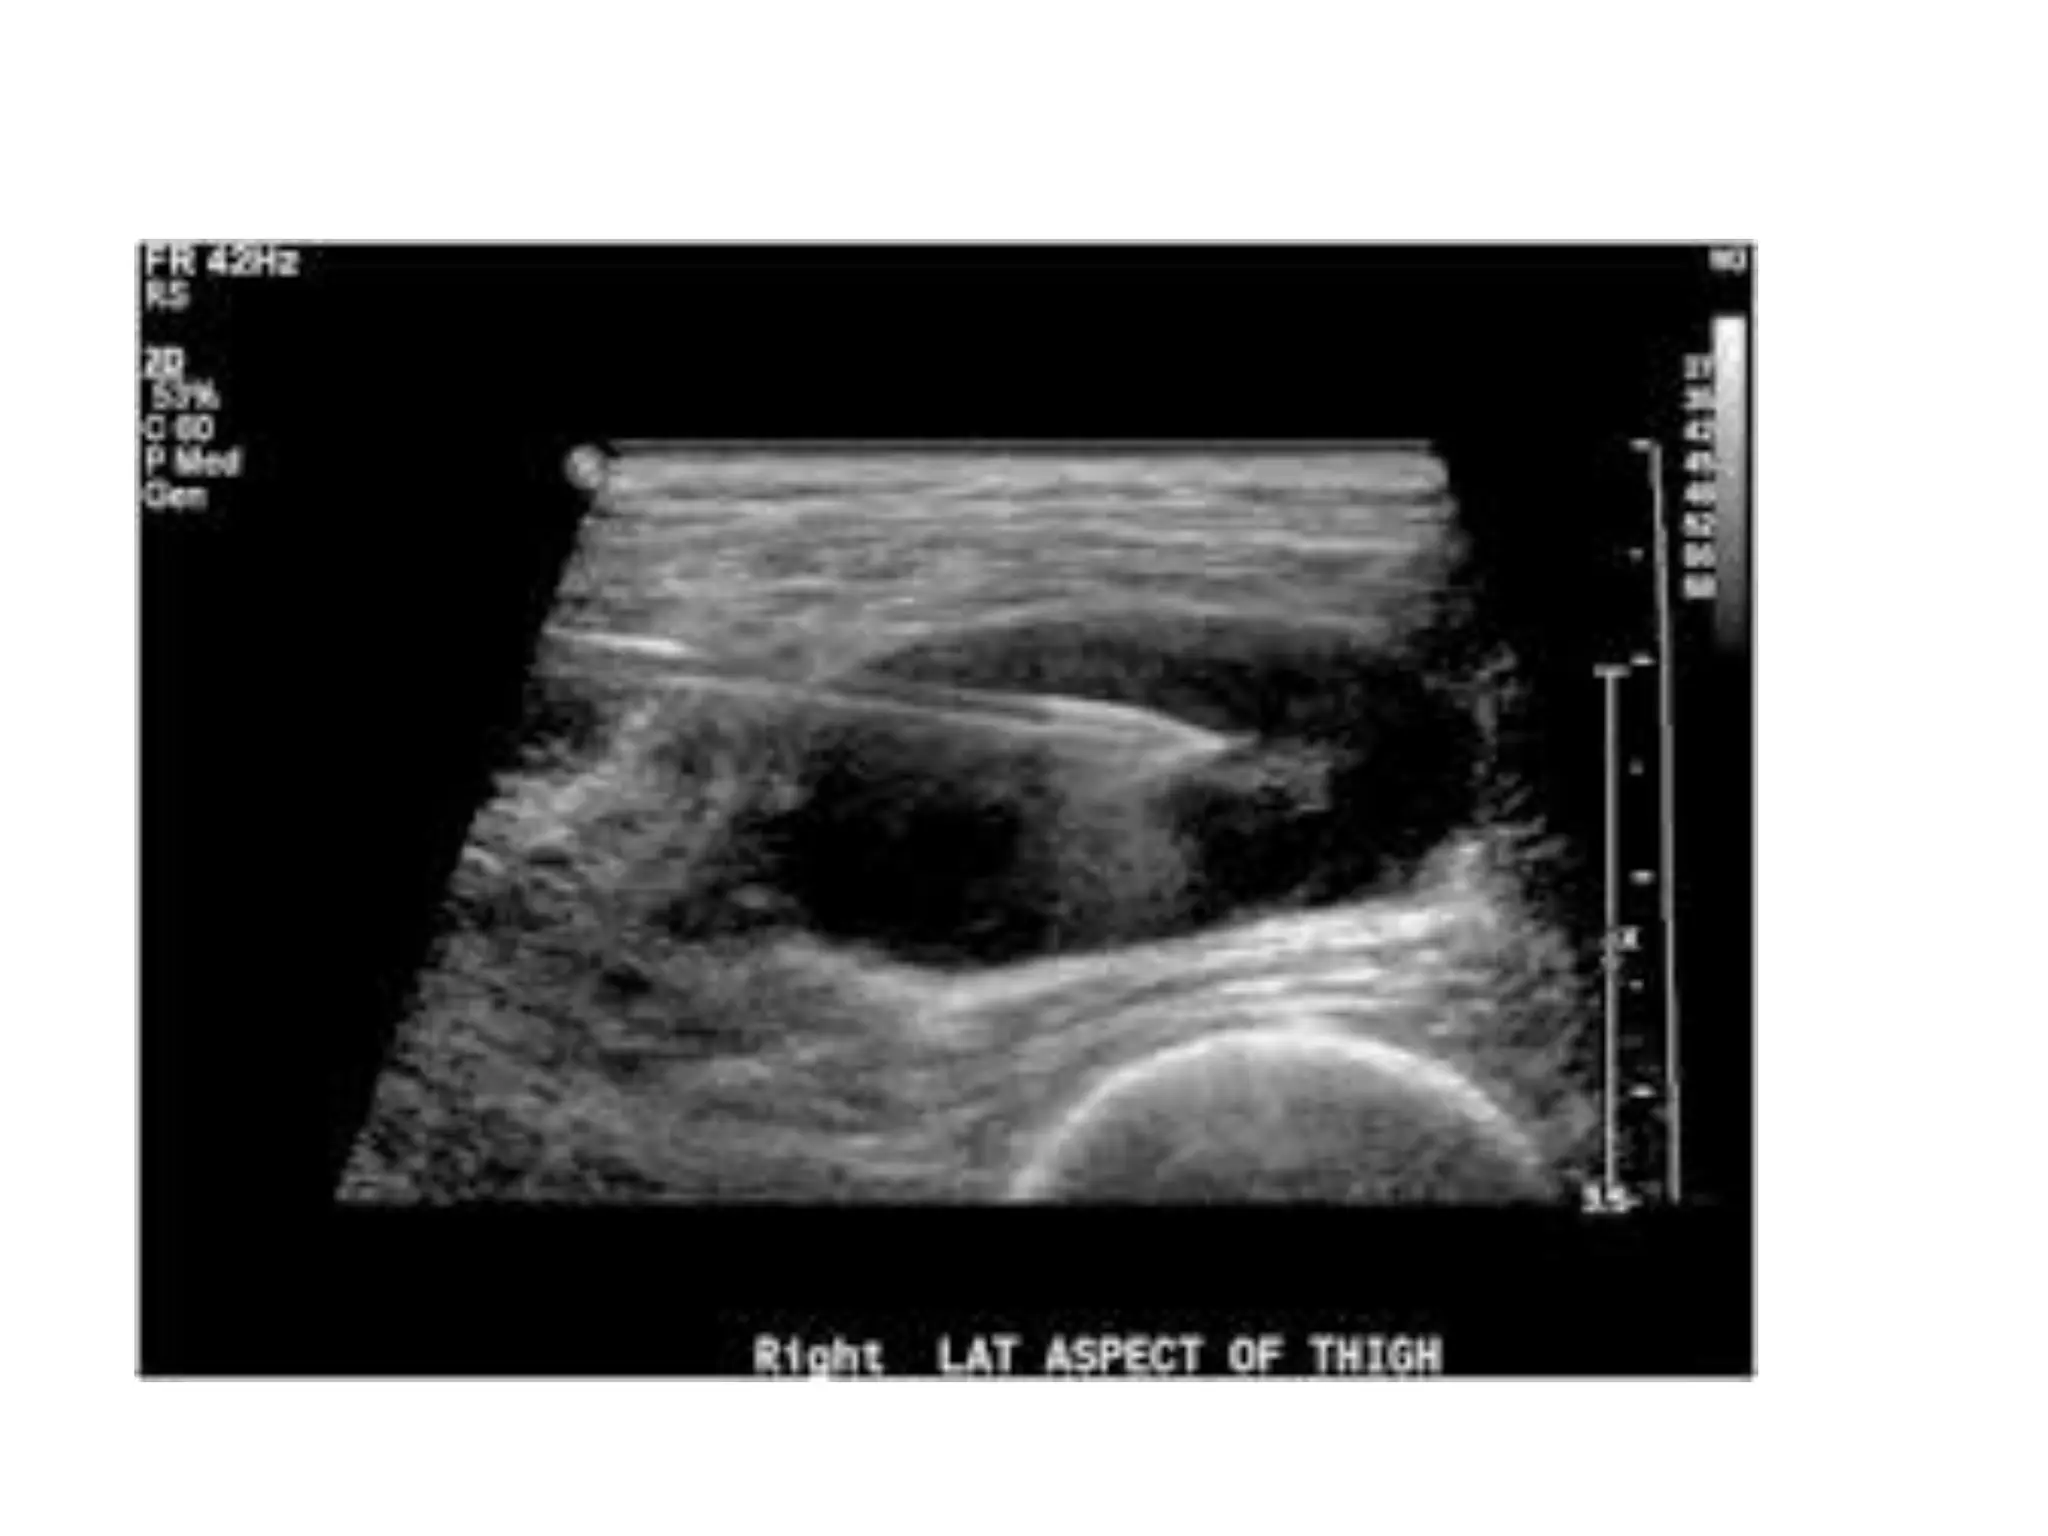

• It is a diagnostic imaging technique

• It is used to create an image of internal body

structures such as tendons, muscles, joints,

blood vessels, and internal organs.

USG Can be used

to evaluate………

Biopsy

• It can show the position of the instrument,

• area to be biopsied

• where to insert the instrument

• It can guide it directly to its target.